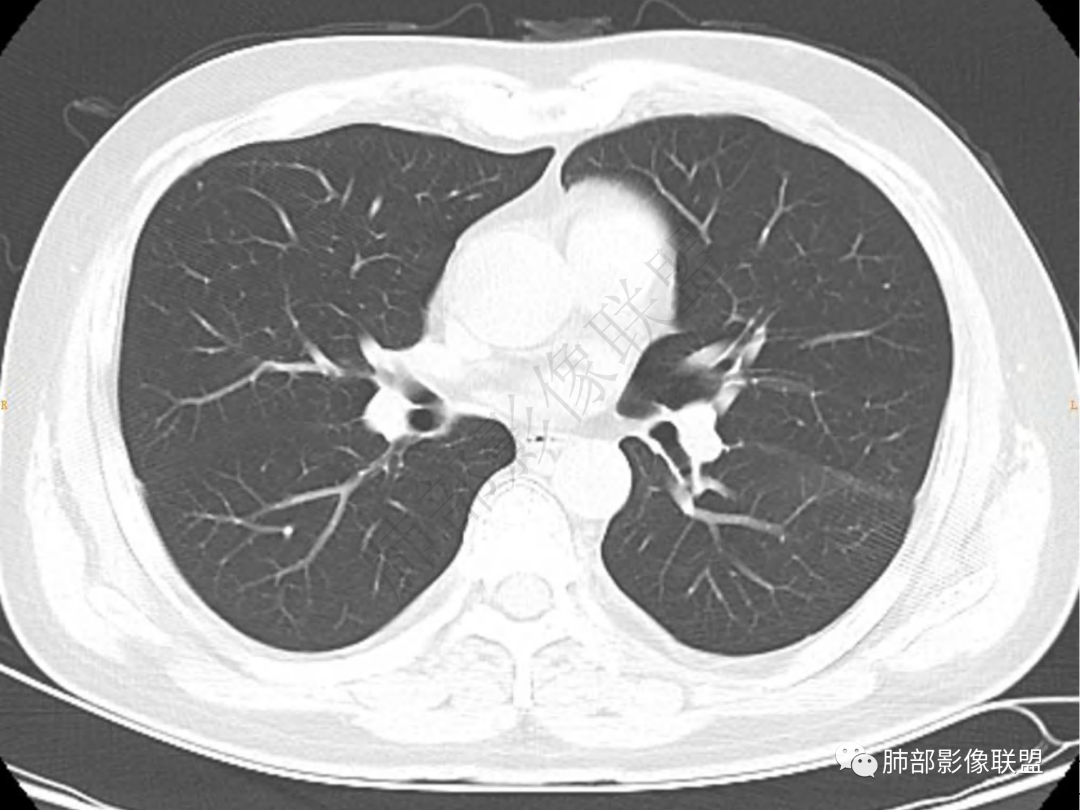

2.左肺下叶团片影,跨背段及内前基底段,实性部分类椭圆形,密度不甚均匀,可见毛刺及棘状突起,未见典型分叶及胸膜凹陷。病灶上下缘可见相应肺段支气管旁进侧出,管壁轻度增厚,未见狭窄阻塞。

3.周边较大范围磨玻璃影,边界相当模糊,小叶增厚明显。注意叶裂另一侧、左肺舌段亦可见磨玻璃影及增厚的小叶间隔。未见明确卫星病灶。

4.实性部分不均匀环形强化并显示一小范围低密度坏死区或空洞。较之肺窗,整体纵隔窗范围较小,提示病灶并不十分密实。抑或为不同时段图像。

5.双肺门及纵隔未见增大淋巴结。未见胸腔积液。